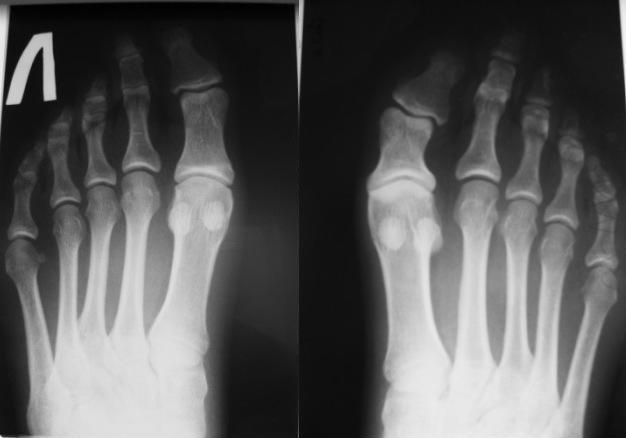

[Ortho] Дисплазия фаланги пальца стопы

Рентгенограммы прилагаю.